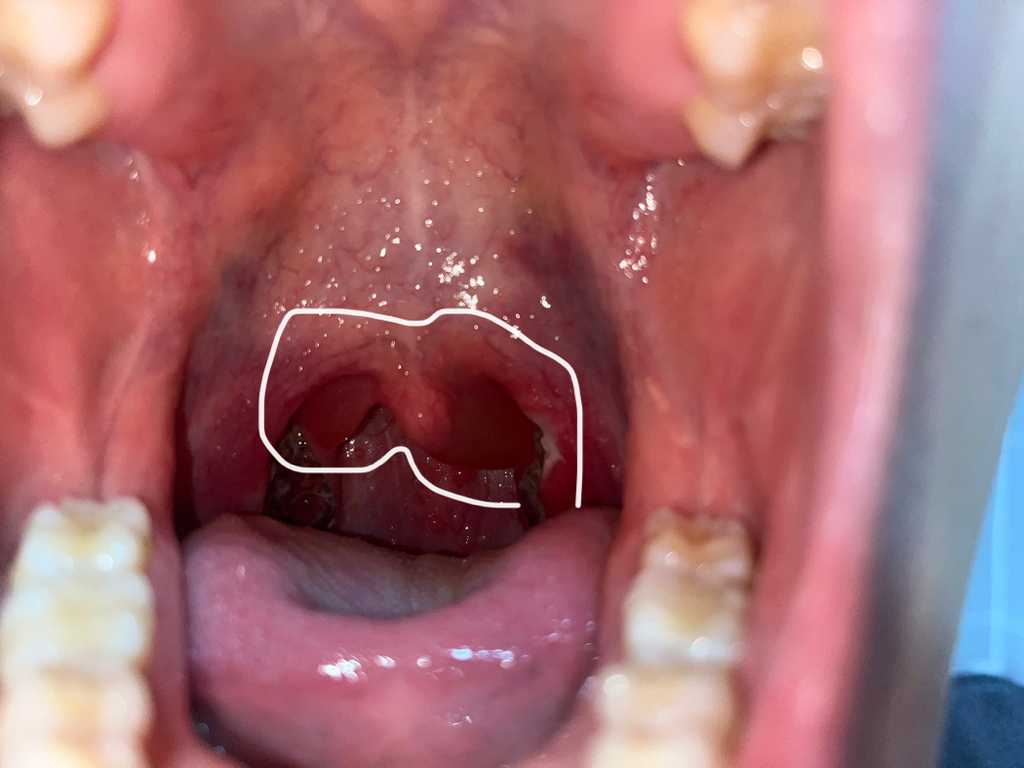

(사진 주의) 편도부분절제술 이후 편도 모양 변이

어제 편도부분절제술을 했는데 목젖 옆살이 늘어나 말하거나 숨을 쉴 때 불편합니다. 수술 후기를 찾아봐도 저와 같은 증상이나 사진을 보이는 분이 없어서 이렇게 여쭙니다. 원래 수술 이후에 저런 식의 변형이 있을 수 있나요? 수술의 부작용인지, 아니면 원래 자주 일어나는 현상인지 궁금합니다.

• 1번 째 사진